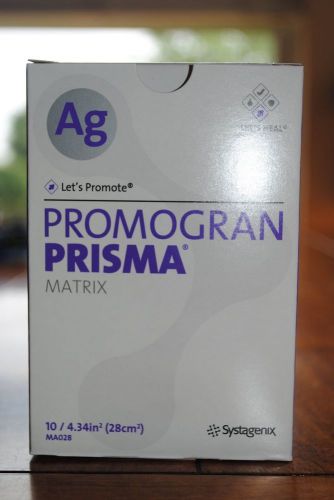

PROMOGRAN PRISMA AG MATRIX MA028--LOT OF 10--SERIOUS BIDDERS ONLY